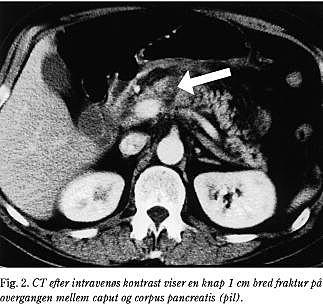

1. En syvårig pige blev indlagt få timer efter et styrt på cykel. Cykelstyret havde ramt den øvre abdomen, og patienten klagede ved indlæggelsen over smerter i epigastriet. Objektivt var hun let smertepåvirket, blodtrykket var på 100/80 mmHg og pulsen på 100. I epigastriet fandtes der et kontusionsmærke, men abdomen var uden diffus peritonealia. Initial UL-scanning viste normale forhold. S-amylase blev ikke undersøgt initialt. Seksten timer efter traumet forværredes tilstanden med hyppige alimentære opkastninger, febrilia (38,2°C), takykardi (120) og S-amylase >4.100 U/l. En fornyet UL-scanning viste fri væske i fossa Douglassi, men fortsat ingen organlæsion. Derimod viste efterfølgende dynamisk CT (Fig. 1), at pancreas var diffust ødematøst for-størret og med ansamling i det peripankreatiske rum, samt at der var en fraktur af pancreas i corpus cauda-overgangen. De øvrige organer var normale. Ved laparotomi fandtes der et hæmatom i mesocolon ud for en subtotal lodret ruptur i corpus pancreatis med overrevet ductus pancreaticus major. Der blev foretaget resektion af den distale del af pancreas. Det postoperative forløb var ukompliceret.

Dynamisk spiral-CT har en sensitivitet på 67-85% for læsioner i pancreas (12, 13). CT-diagnosen bygger dels på specifikke tegn: synlig pancreasfraktur, pancreashæmatom eller -forstørrelse, væske mellem vena lienalis og pancreas eller peripankreatisk hyperdensitet, og dels på uspecifkke tegn; fortykket Gerotas fascie, væske i lille sæk eller anden peritoneal væske, ekstraperitoneal væske eller andre organlæsioner (fx milten) i regionen. Selv alvorlige pancreaslæsioner med ductuslæsion kan dog være CT-negative i den akutte fase (14). CT'en viste i alle tre sygehistorier såvel specifikke som uspecifikke tegn, men kun i sygehistorie 1 og 2 fik patienten foretaget eksplorativ laparotomi på dette grundlag.